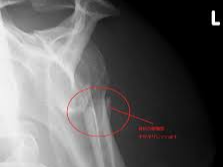

어깨에 골절이 발생하면 일상 전체가 마비되는 기분을 느끼는 것도 무리는 아닙니다. 특히 쇄골, 상완골 근위부, 견갑골 부위에 골절이 생기면 수술이 필요하며, 수술 이후의 재활과 물리치료는 단순히 통증을 없애는 것을 넘어, 관절 가동 범위의 회복과 장기적인 기능 정상화를 위한 핵심 단계입니다. 또한 어깨 골절 수술 이후 본격적으로 시작되는 재활 치료와 도수치료의 현실적인 문제는 ‘비용’과 ‘보험 적용 여부’입니다.